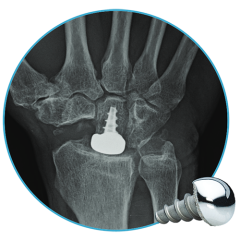

Explore our broad range ofOrthopedic Products

We are dedicated to improving the quality of life of patients suffering with bone and joint problems by delivering the latest medical devices that are proven to be effective and backed by scientific studies and research

• Surgical Devices